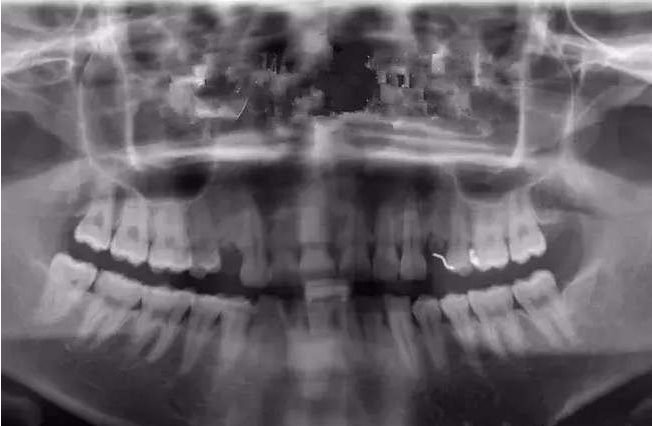

诊断也不是看看就完了,有的还需要通过CT来进行多个方向的诊断分析,并判断严重程度。对于牙齿的排列、拥挤度的测量还可以通过模型来分析。